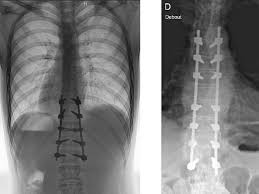

Prise En Charge Des Fractures A Haute Et Basse Energie Traumatique De La Colonne Thoracique Et Lombaire Revue Medicale Suisse

Prise En Charge Des Fractures A Haute Et Basse Energie Traumatique De La Colonne Thoracique Et Lombaire Revue Medicale Suisse from www.revmed.ch